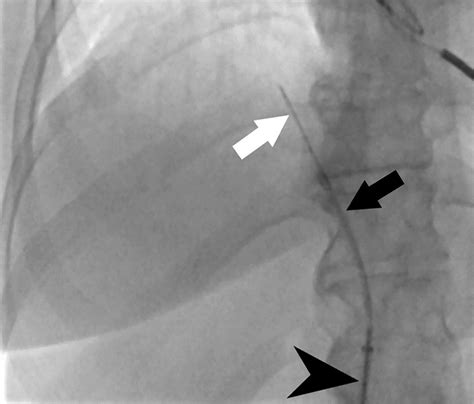

Learn About The Liver Biopsy & Its Procedure - The GI Docs

Liver Biopsy: Understanding Test Purpose and Results Enlarged liver - Diagnosis & treatment - Mayo Clinic Learn About The Liver Biopsy & Its Procedure - The GI Docs Liver Biopsy for Detection of Liver Disease in Baltimore at Mercy How My Liver Biopsy Results Helped Diagnose My PSC TJ Liver Biopsy — The Interventional Initiative What is liver biopsy Procedure? [Steps & Cost] Liver biopsy Liver Biopsy Procedure: A Breakthrough in Liver Health Percutaneous and Transvenous Liver Biopsy • APPLIED RADIOLOGY Look beyond liver biopsy for NAFLD diagnosis | MDedge Internal Medicine Percutaneous and Transvenous Liver Biopsy • APPLIED RADIOLOGY Liver Biopsy - drchetankalal Liver biopsy procedure | Media Asset | NIDDK Mua Biopsy Interpretation of the Liver (Biopsy Interpretation Series How Liver Biopsy Is Performed? - E-Healthy Info Liver Biopsy-Suzhou Leapmed Healthcare Corporation What to Expect at your Ultrasound-Guided Liver Biopsy The Liver Biopsy: Importance and Interpretation | AASLD SOLUTION: paracentesis liver biopsy - Studypool liver biopsy color icon vector illustration Stock Vector Image & Art Liver Biopsy Interpretation: Special Stains | AASLD Liver Biopsy Interpretation: Special Stains | AASLD Liver function tests in primary care - bpacnz PPT - Biliary Atresia PowerPoint Presentation, free download - ID:1199110 LIVER BIOPSY by Dr. Robert Gish - YouTube Laparoscopic Liver Biopsy Procedure | #shortvideo #liverbiopsy - YouTube Biopsy Interpretation of the Liver Buch versandkostenfrei bei Weltbild.de Biomolecules | Free Full-Text | The Current Status of the Liver Liquid Liver steatosis induces portal hypertension regardless of fibrosis in